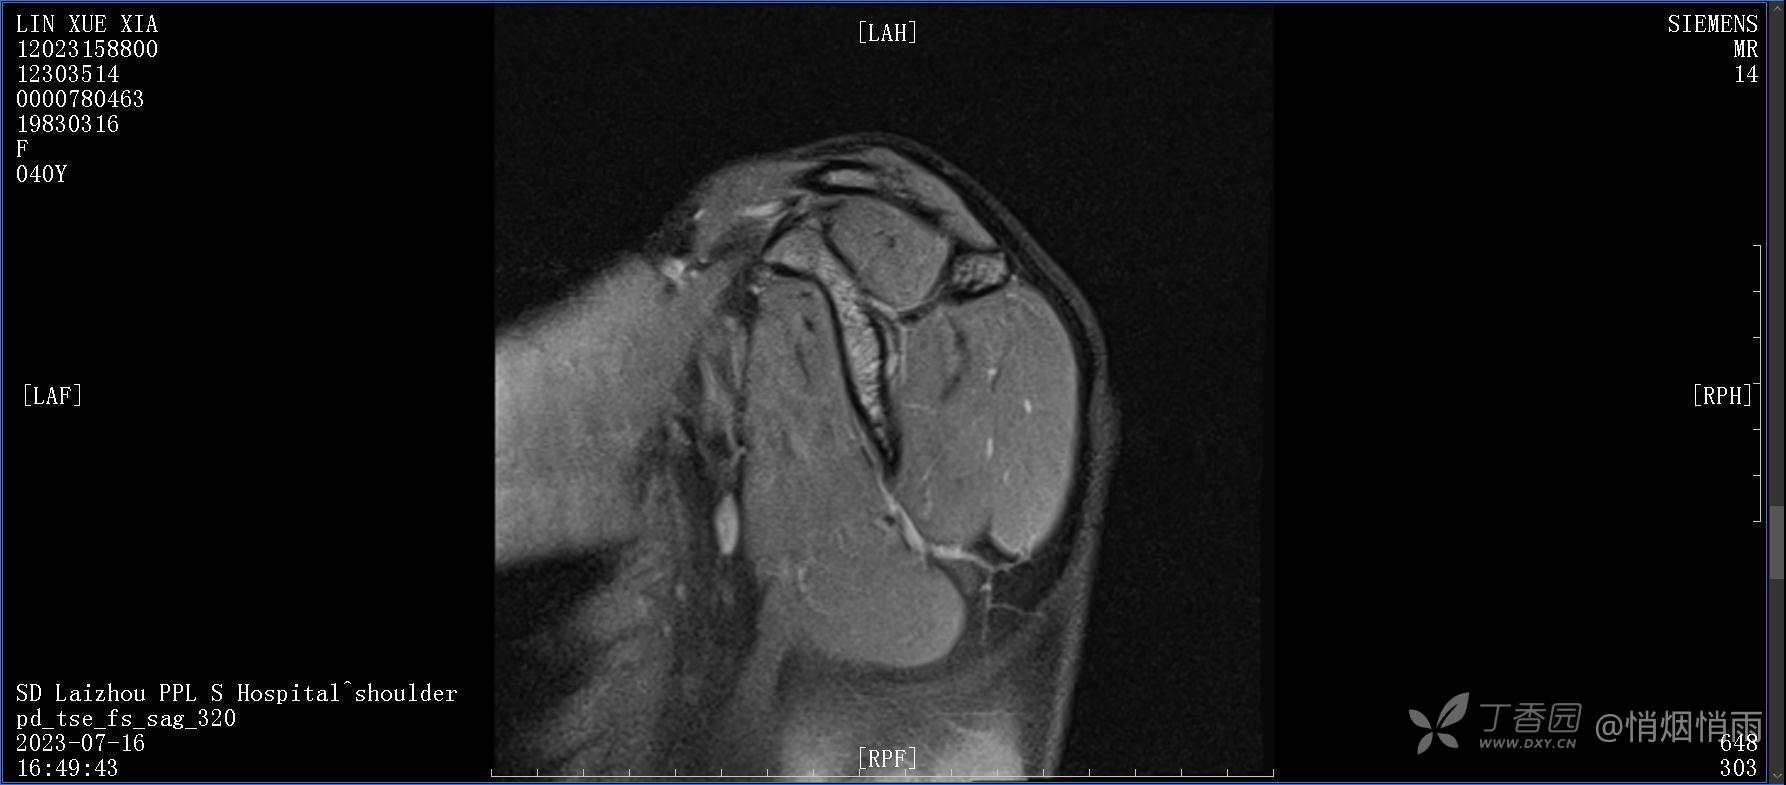

查体:右肩关节局部轻度肿胀,肩胛区压痛明显,痛处不固定,肩关节痛性活动受限,jobe test(+),lift -off test(+),中指、环指感觉较余指减退,余肢端感觉及血运情况可。

目前的诊断,暂时依据辅助检查诊为肩袖损伤,但是患者疼痛的性质和特点,却不是单纯的肩袖损伤所致。考虑过胸廓出口综合征,但是该疾病会出现肩胛区的疼痛吗?(由于考虑到费用的问题,没再进行下一步的检查)带状疱疹会有如此的症状吗?